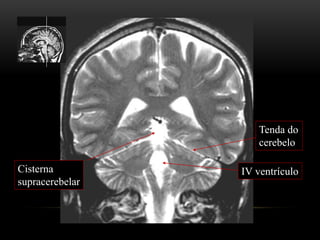

ANATOMIA TOPOGRÁFICA

Plano coronal

Tenda do

cerebelo

Cisterna

supracerebelar

IV ventrículo